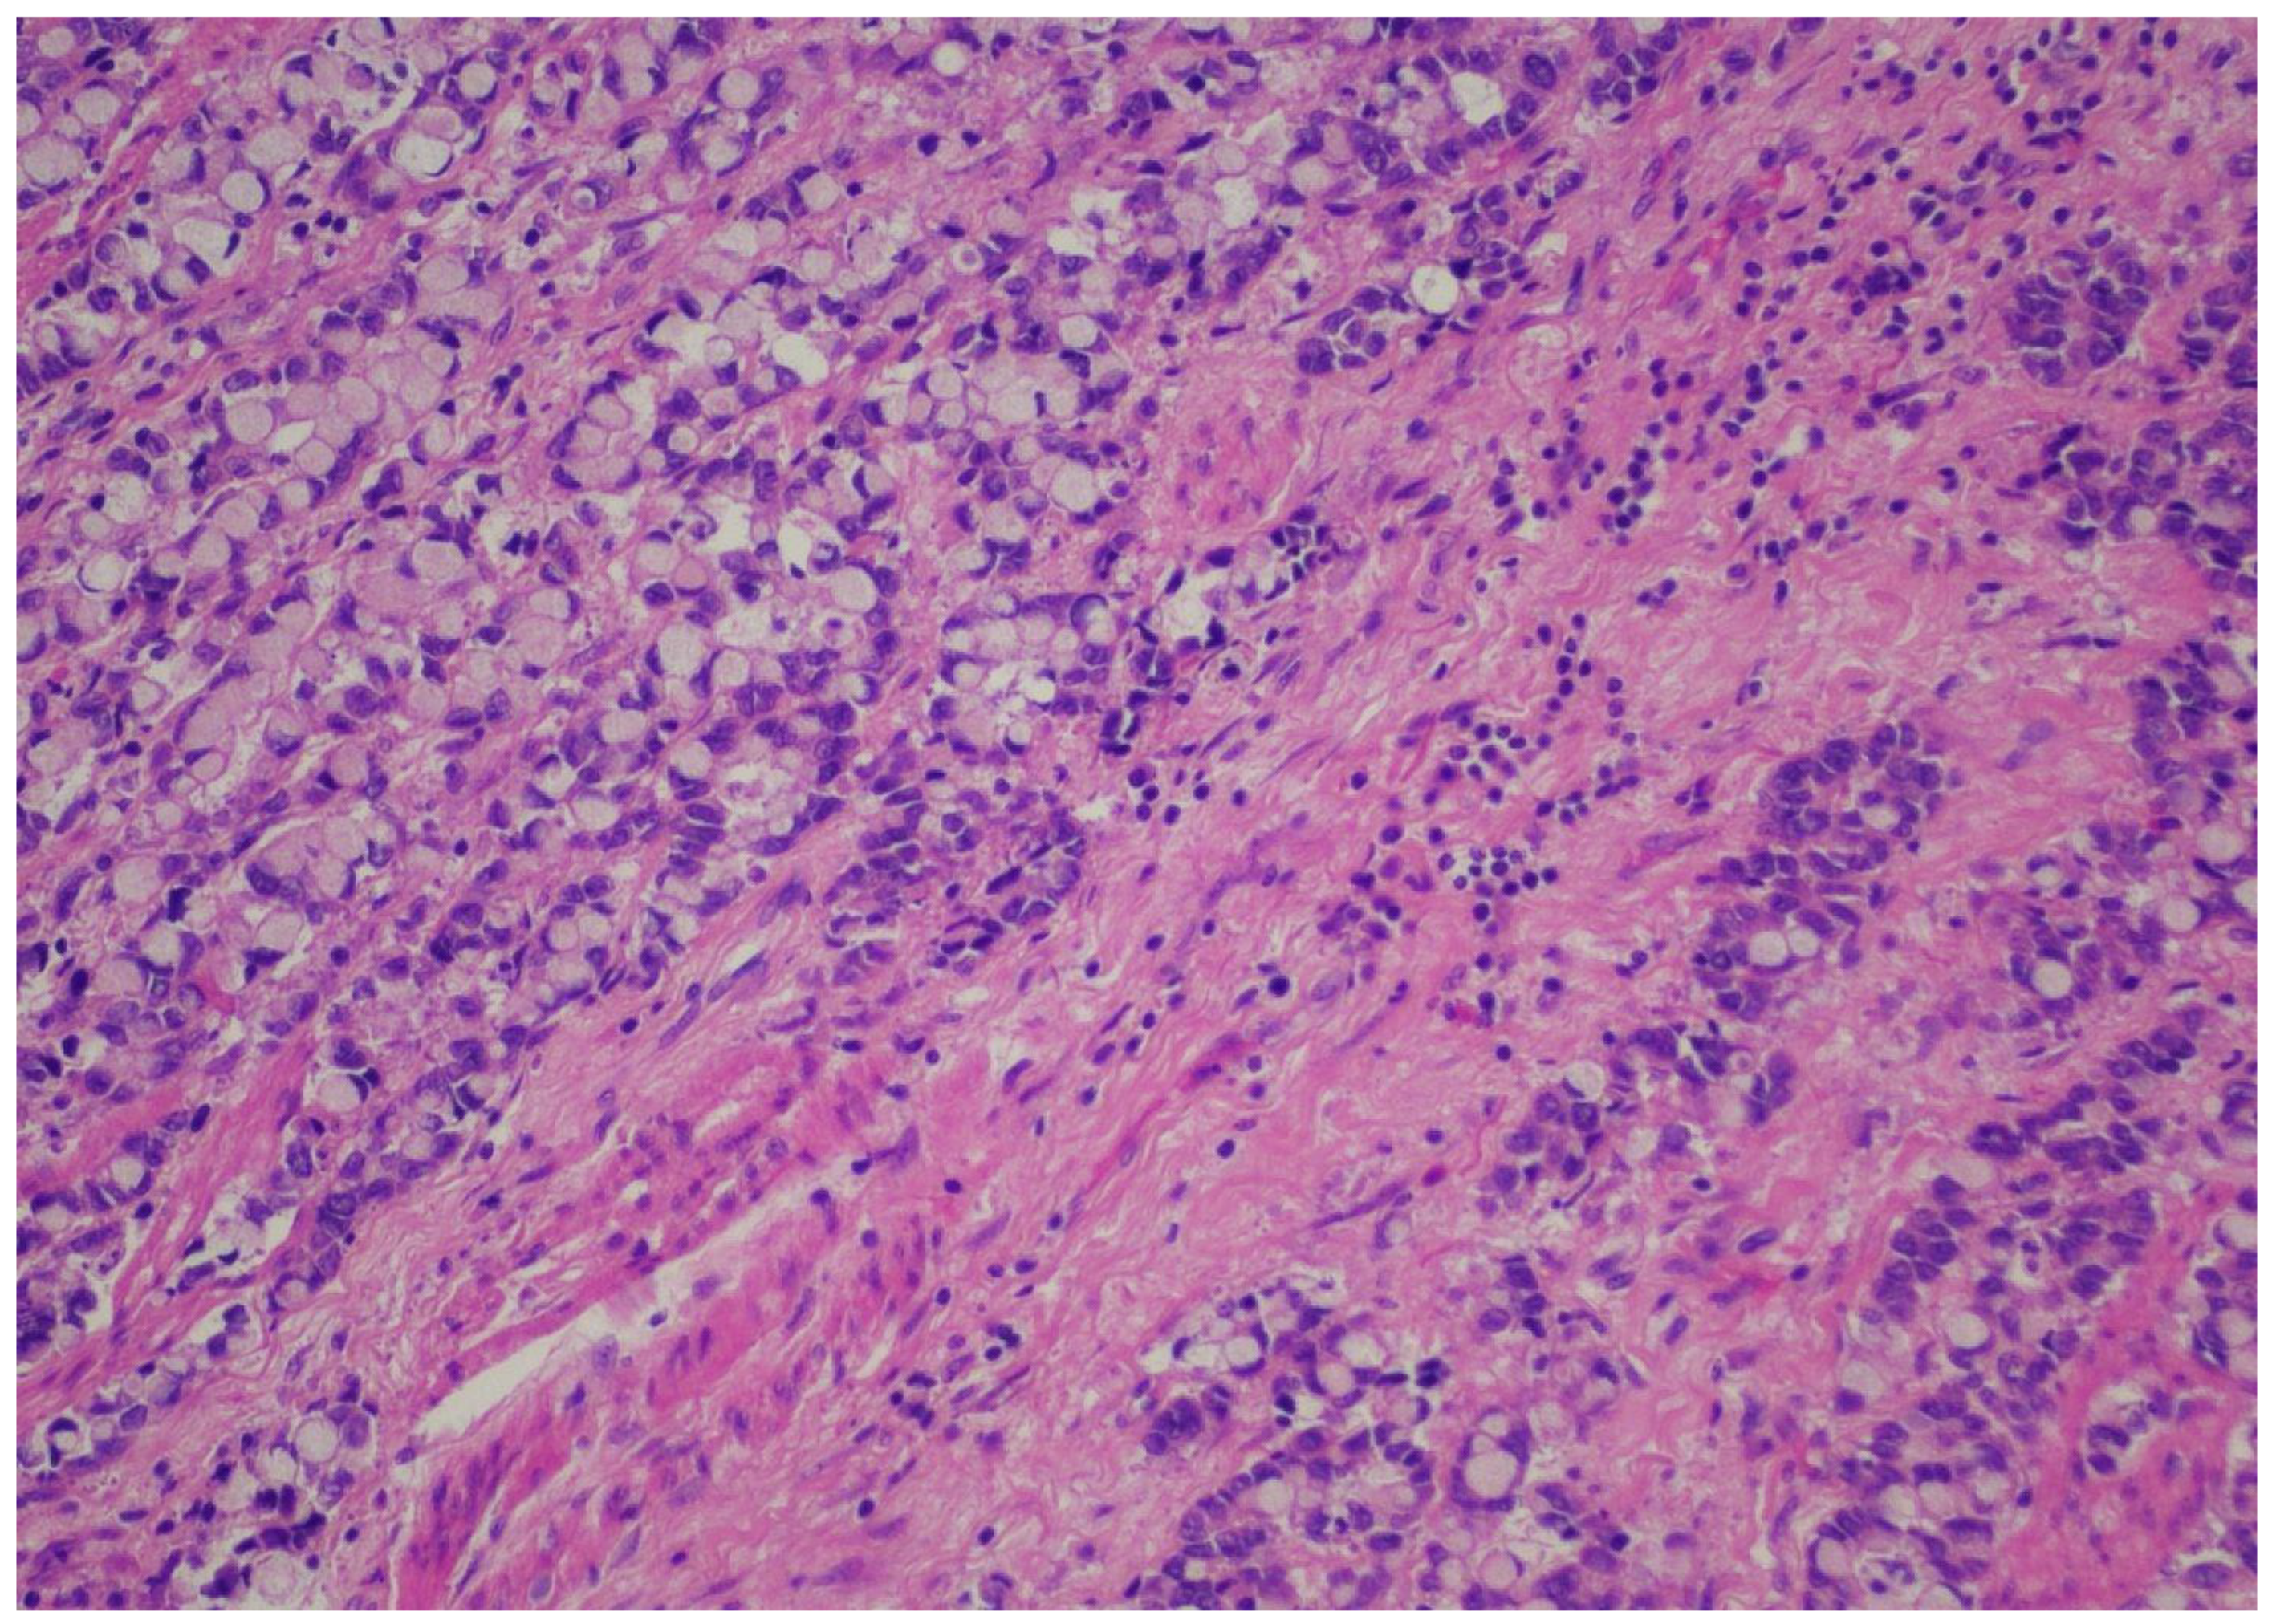

Records from patients with gastric or esophageal adenocarcinoma operated on in a single academic institution during the time period from January 2022 until January 2024 were reviewed after institutional review board permission. Demographics, including age and gender, were recorded for all patients. Only patients with adenocarcinomas who underwent esophagectomy or gastrectomy according to respective tumor location were included. Only patients who were operated on after the completion of the neoadjuvant FLOT regimen were included in the analysis. Type of operation performed and pathology reports/relevant pathology slides were reviewed, including total number of lymph nodes, positivity or negativity of lymph nodes, node positivity after regression, and node negativity with regression. Tumor regression (TRG) score was reported according to the Mandard classification [21]. TRG values ranged from 1–5, with 1 designating no residual cancer cells, TRG 2 residual cancer cells, TRG 3 fibrosis outgrowing residual cancer, TRG 4 residual cancer outgrowing fibrosis, and TRG 5 absence of regressive features. Staging was performed according to the American Joint Commission on Cancer (AJCC), 8th edition [22]. All relevant slides were also reviewed to calculate TIL scores for all patients, expressed as a numerical score, according to relevant guidelines from international consortia on tumor-infiltrating lymphocytes [23]. When no tumor could be identified after neoadjuvant treatment, by definition, no TIL scores could be assigned. More specifically, a review of the pathology slides measurement of TILs did not require any stains on the slides but rather only calculating TIL scores from “measuring” the number of lymphocytes relevant to the tumor. The reader is directed to the aforementioned reference for the exact protocol used to calculate TIL scores. Pathology reports for all relevant operations were reviewed, and pathology slides were re-reviewed by 2 independent expert pathologists (CG and DR) to calculate the TIL score. A TIL score from 0–80 was granted, and where no tumor was found, “no tumor” was designated for TIL score calculations. Figure 1 and Figure 2 depict slides from our patient cohort, with the first corresponding to a TIL-high patient, while the latter originates from a TIL-low patient.

The SPSS package [IBM SPSS statistics version 29.0.2.0(20)] was used for all statistical analyses. In order to create subgroups of TIL patients of sufficient sample size, we created two groups for TILs, namely TIL-low and TIL-high groups, with the TIL-low group containing scores from 0–30 and the TIL-high group containing numbers from 40–80. Representative pictures from pathologic slides from our patient series are provided in pictures 1 (TIL-low) and 2 (TIL-high). We affirmed that both TIL-low and TIL-high groups contained more than 25 patients each, and therefore, by definition, we assumed that the sample size followed a normal distribution and included categorical data; thus, Spearman’s r correlative statistic could be used for analysis. With regards to the Mandard score, we stratified patients into a “good response” TRG1 and TRG2 and a “bad response” TRG 3, TRG 4, and TRG 5. Correlation analysis between TRG and the TIL-low or TIL-high group was performed using the Spearman’s r statistic and Kendall’s tau statistics.

Figure 2. TIL-low patient.